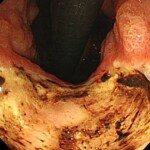

@痛み止めによる胃潰瘍

@胃の不調により胃薬で改善せず、胃カメラをしたら「スキルス胃がん」